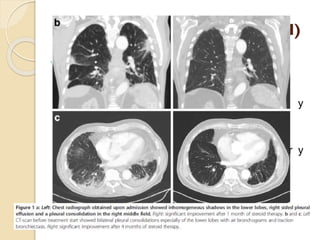

AFECTACIÓN PLEURAL



Estudio Zen et al:

◦ El 24% de los pacientes presentaban afectación

pleural.

Lesiones nodulares en la pleural visceral

y parietal.

Efusión pleural.

Pleuritis.